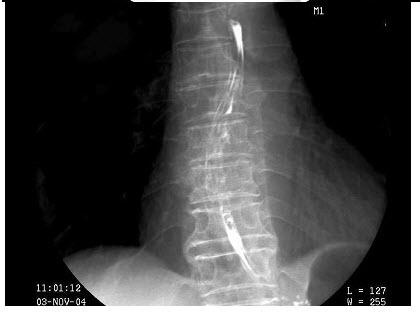

126、单项选择题

椎间盘脱出的部位常见于()

A.C1-2

B.T3-4

C.L1-2

D.C7~T1

E.L5~S1